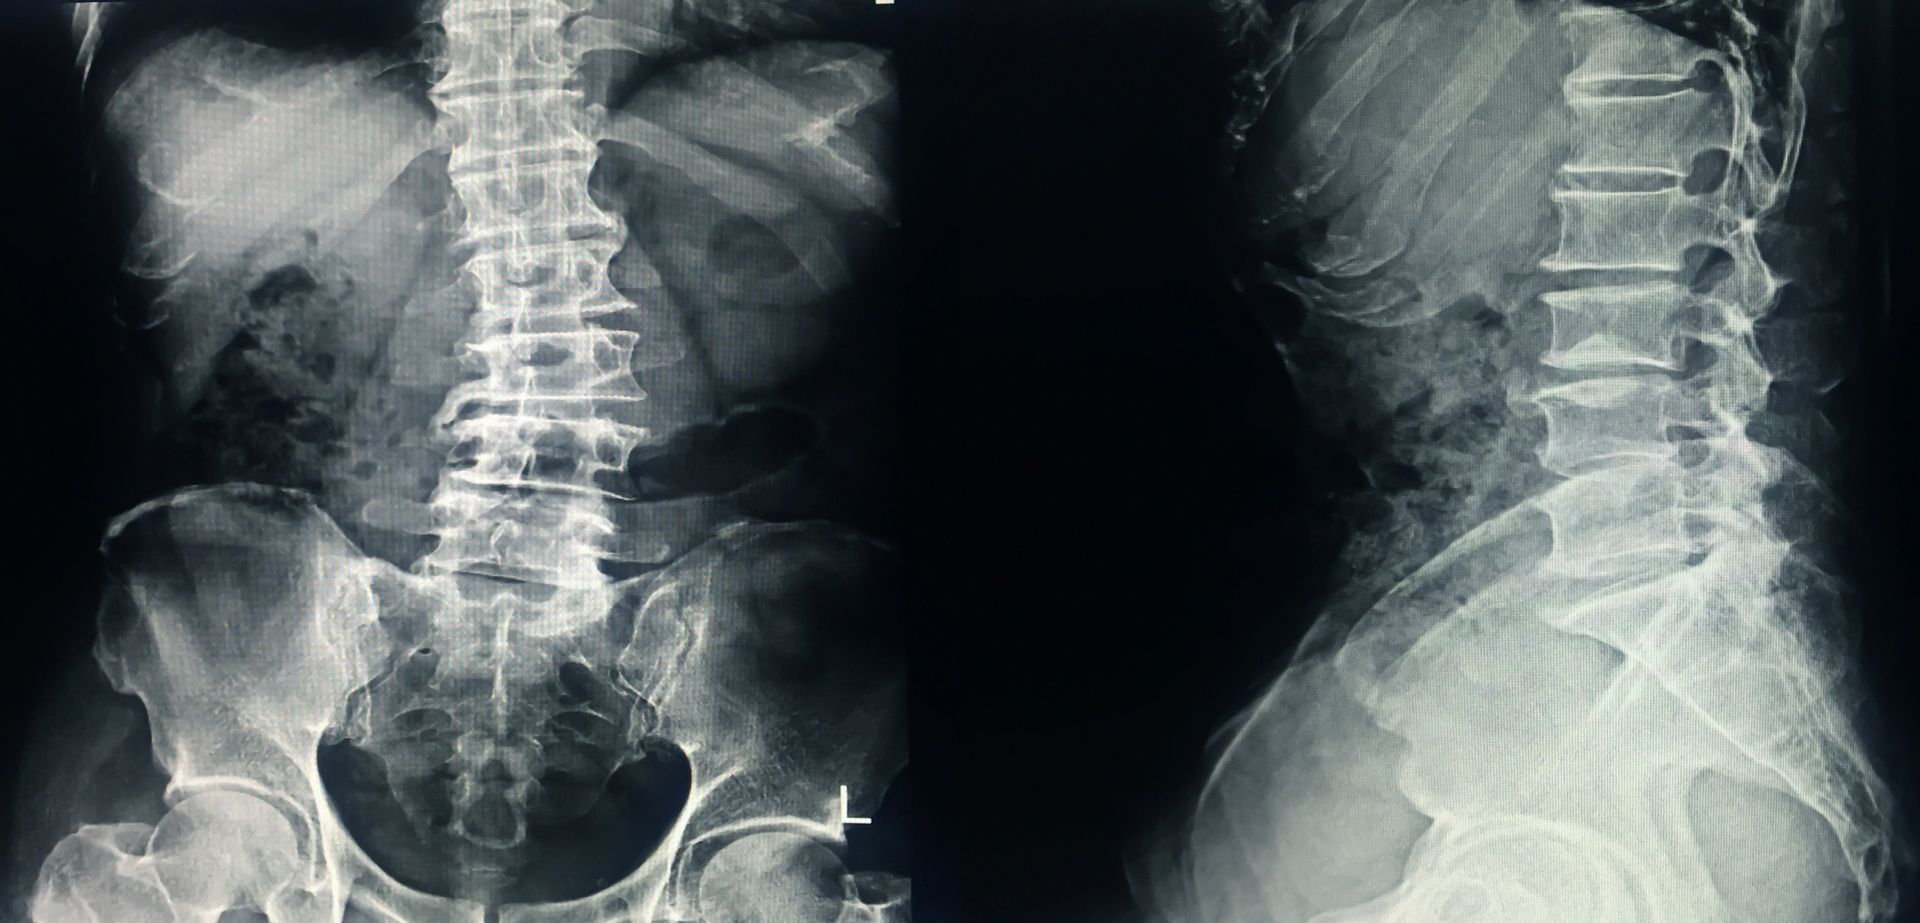

Radiografia della colonna vertebrale

Il rachide in ortostasi è un esame radiologico fondamentale per valutare l’allineamento della colonna vertebrale quando il paziente si trova in posizione eretta. Questa modalità di indagine è particolarmente utile per identificare alterazioni posturali come scoliosi, ipercifosi o iperlordosi, condizioni che si manifestano con maggiore evidenza quando il corpo mantiene la sua naturale postura quotidiana. L’esame viene spesso prescritto nei giovani e negli adolescenti, fascia d’età in cui la colonna è ancora in sviluppo e può presentare variazioni strutturali che richiedono monitoraggio. Il test consente di ottenere immagini precise e complessive del rachide, contribuendo a un inquadramento diagnostico accurato e alla definizione di eventuali percorsi terapeutici o riabilitativi.

Durante l’esame il paziente viene posizionato a due metri dalla sorgente radiografica, con le braccia flesse a circa 45 gradi e le mani appoggiate su un apposito supporto. È fondamentale mantenere la testa dritta e rimanere immobili per tutto il tempo necessario all’acquisizione delle immagini. Il tecnico radiologo guida ogni fase, spiegando come assumere la posizione più corretta per ottenere un’immagine chiara e facilmente interpretabile. L’intera procedura dura pochi minuti e non provoca dolore o fastidio. Le immagini ottenute consentono al medico di visualizzare allo stesso tempo segmenti cervicali, dorsali e lombari per valutare in modo completo l’intera colonna.

Le patologie più frequentemente analizzate includono scoliosi, ipercifosi dorsale, iperlordosi lombare e altre condizioni legate alla crescita o a squilibri muscolari. L’esame permette anche di osservare eventuali rotazioni vertebrali, dismetrie del bacino e alterazioni dell’asse corporeo che possono influenzare la postura generale. Nei giovani rappresenta uno strumento di controllo importante per monitorare l’evoluzione di eventuali curvature anomale durante gli anni di sviluppo, mentre negli adulti può essere utile per valutare problematiche croniche o degenerative. La visualizzazione completa del rachide consente una valutazione oggettiva e facilmente confrontabile con esami successivi.